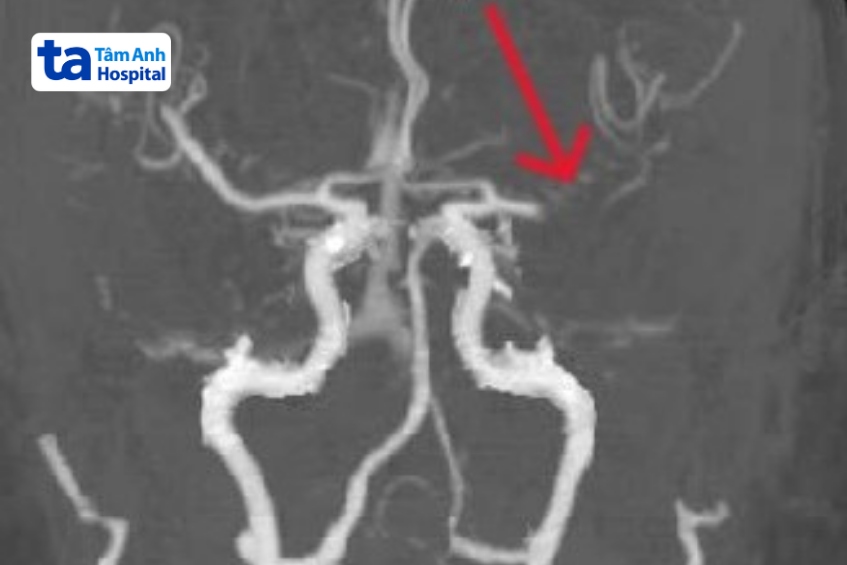

Kết quả chụp CTA mạch máu não phát hiện cụ Năm bị tắc hoàn toàn động mạch não giữa bên trái tại vị trí nhánh M1, chiều dài khoảng 10 mm. Ngay lập tức, cụ được chuyển ngay đến phòng DSA (Digital Subtraction Angiography) để can thiệp nội mạch, loại bỏ cục huyết khối đang làm tắc động mạch não.